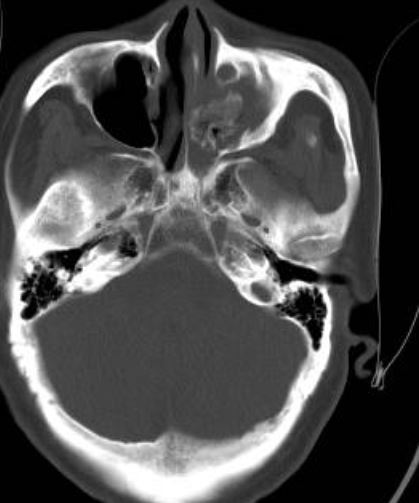

真菌性鼻竇炎又稱(chēng)為霉菌性鼻竇炎,是鼻科臨床上一種特殊類(lèi)型的鼻竇炎。根據(jù)是否有侵襲性又分為侵襲性真菌性鼻竇炎和非侵襲性真菌性鼻竇炎。 侵襲性真菌性鼻竇炎多半發(fā)生在免疫缺陷的患者,按病程緩急和臨床特征又分為急性侵襲性和慢性侵襲性,此類(lèi)型病理特征是真菌感染從鼻腔鼻竇內(nèi)侵犯周?chē)]壁黏膜和骨質(zhì),累及眼眶、顱底等周?chē)Y(jié)構(gòu),治療以手術(shù)清除病變,積極抗真菌治療為原則,由于這種類(lèi)型的患者多半免疫力很差,短時(shí)間又無(wú)法提升,所以預(yù)后較差。 而非侵襲性真菌性鼻竇炎根據(jù)類(lèi)型有分為真菌球和變應(yīng)性真菌性鼻竇炎兩種。真菌球型多半發(fā)生在中老年女性,單側(cè)鼻竇發(fā)病,尤其是上頜竇最為多見(jiàn),臨床表現(xiàn)為單側(cè)頭疼、牙疼、面頰疼痛、流涕、涕中帶血、鼻堵、嗅覺(jué)減退、鼻腔異味,也有患者沒(méi)有任何臨床癥狀,是在進(jìn)行頭顱CT、核磁檢查時(shí)無(wú)意中發(fā)現(xiàn)的,但一旦急性發(fā)作會(huì)出現(xiàn)劇烈頭疼,患者會(huì)到急診就診,口服止痛片緩解癥狀,所以發(fā)現(xiàn)問(wèn)題要及時(shí)治療。治療上以手術(shù)治療為主,手術(shù)在內(nèi)鏡下進(jìn)行,術(shù)中打開(kāi)鼻竇,清除竇腔內(nèi)的真菌團(tuán)塊(見(jiàn)下圖),手術(shù)效果較好,復(fù)發(fā)比例很低。 而變應(yīng)性真菌性鼻竇炎則好發(fā)于中青年,可單側(cè)雙側(cè)均可發(fā)病,患者多為過(guò)敏體質(zhì),可合并哮喘,真菌的過(guò)敏原檢查常呈陽(yáng)性,治療以手術(shù)治療加上術(shù)后長(zhǎng)期的激素等藥物治療為原則,此病極易復(fù)發(fā),手術(shù)后一定要叮囑患者長(zhǎng)期、定期隨診用藥。 無(wú)論是真菌球還是變應(yīng)性真菌性鼻竇炎都不推薦全身使用抗真菌藥物。 標(biāo)本瓶?jī)?nèi)是術(shù)中取出的真菌團(tuán)塊,像豆腐渣一樣,這是典型的真菌球型鼻竇炎的表現(xiàn),手術(shù)效果很好。

雖然真菌性蝶竇炎的發(fā)病率較真菌性上頜竇炎要低,但其臨床癥狀(頭痛、涕倒流、回吸涕血)和可能出現(xiàn)的并發(fā)癥更為嚴(yán)重(視力下降,動(dòng)眼神經(jīng)麻痹,海綿竇綜合征,顱內(nèi)真菌感染),因此準(zhǔn)確的通過(guò)影像學(xué)去診斷和鑒別診斷,有助于盡早的確診和手術(shù)干預(yù)。換句話說(shuō),對(duì)于單獨(dú)的上頜竇炎和單獨(dú)的蝶竇炎,后者應(yīng)更重視。真菌性蝶竇炎在CT上表現(xiàn)為蝶竇內(nèi)軟組織密度影伴高密度影,該表現(xiàn)在軟組織窗比較典型,骨窗圖像中可不明顯,有可能無(wú)法直接確診,但可觀察到蝶竇各壁有骨炎反應(yīng)性骨質(zhì)增厚的間接征象。對(duì)于不典型的病例可以通過(guò)MRI來(lái)鑒別診斷。真菌性鼻竇炎的特點(diǎn)是周邊水腫黏膜為長(zhǎng)T2信號(hào),竇腔內(nèi)病變主體為短T2信號(hào),表明含水量較少(或順磁性差),合并炎癥時(shí)為等T2長(zhǎng)T2混雜信號(hào)。T1上真菌病變?yōu)榈刃盘?hào)。T1+C增強(qiáng)像為中央低信號(hào),周?chē)つび袕?qiáng)化。合并細(xì)菌感染炎癥較重的病例由于竇腔內(nèi)壓力較高,竇口可增寬向鼻腔側(cè)膨出,內(nèi)鏡下可見(jiàn)竇口前方黏膜水腫息肉樣變及膿性分泌物。